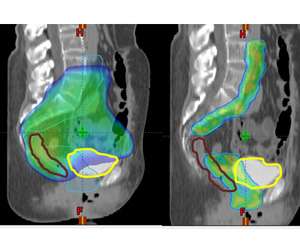

IMRT is a treatment advance that allows us to modulate the intensity of the radiation dose within a given radiation field. This means that the distribution of the radiation dose can be sculpted more finely around targets of interest while sparing more normal tissues. An example of this can be seen below where the axial CT image on the left is an example of a 3D-conformal plan and on the right is an example of an IMRT plan on the same patient. One can see that the IMRT plan allows the majority of the dose to be placed around the lymph nodes (which is the target) while sparing the bowel centrally.

Here at UCLA we have multiple state of the art radiation treatment machines that are capable of IMRT. These include: Tomotherapy, TrueBeam, NovalisTX, and ViewRay. Because the radiation dose is more sculpted with IMRT it is critical that the patient be set up properly each day. Image guidance (IGRT) is used to verify your position and anatomy prior to your treatment to ensure that the intended radiation targets are being treated properly. Any adjustments in your setup are made and then when 100% certainty is achieved the treatment is delivered.